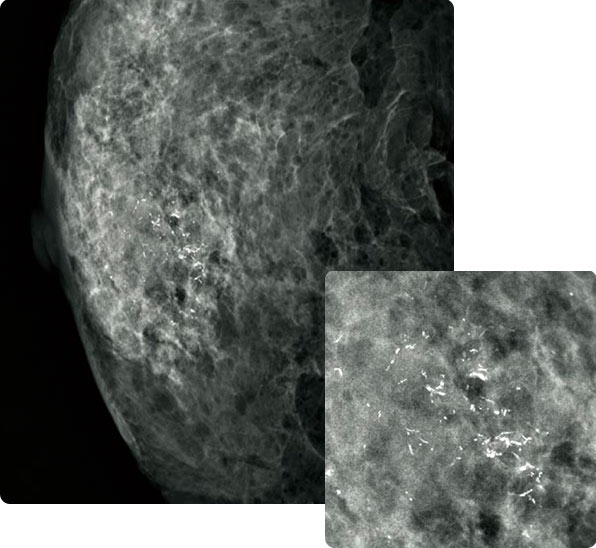

Шестиугольный пиксел в системе AMULET

Плоскопанельный детектор с матрицей гексагональной сплошной структуры (HCP) эффективно регистрирует электрические сигналы, полученные путем преобразования рентгеновского излучения, обеспечивая высокое разрешение и низкий уровень шума. Благодаря этой конструкции удалось достичь более высокого показателя квантовой эффективности детектора (DQE), чем в обычных TFT-панелях с матрицей из квадратных пикселов. На основе информации, полученной детектором HCP, система AMULET Innovality создает изображения высокой четкости с размером пиксела не более 50 мкм — на данный момент это максимальное разрешение, имеющееся на детекторах с прямым преобразованием сигнала.

Эта технология с низким уровнем шума и высокой скоростью срабатывания дает возможность проводить съемку в режиме томосинтеза с низкой лучевой нагрузкой и коротким временем получения готового исследования. Также возможен быстрый вывод изображений на экран, что обеспечивает беспрепятственное выполнение всего маммографического исследования, от съемки до просмотра изображений.